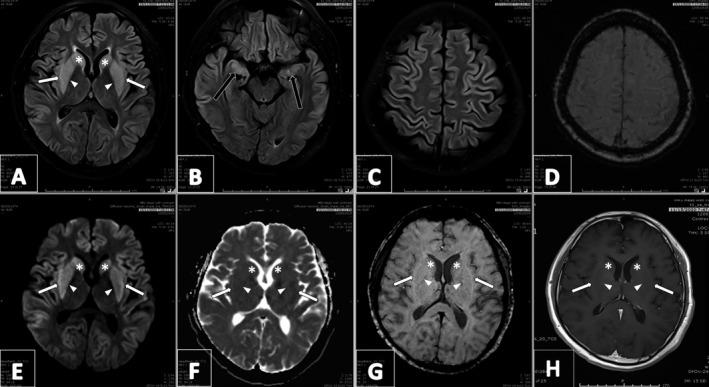

Until we have strong evidence to the contrary, symptomatic hyponatremia should be treated with extra caution in COVID-19 co-infection patients as the latter could be another risk factor for the development of extrapontine myelinolysis.